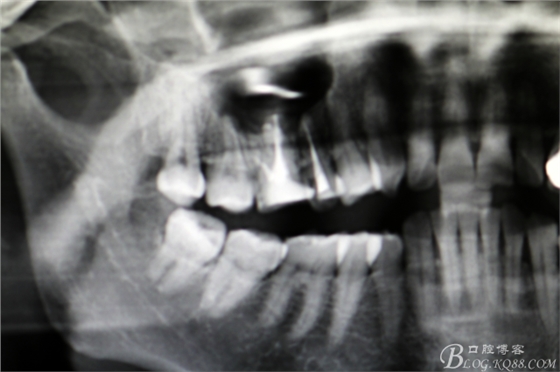

圖21.局部放大影像:16腭根做根尖切除,近頰根行MTA倒充填